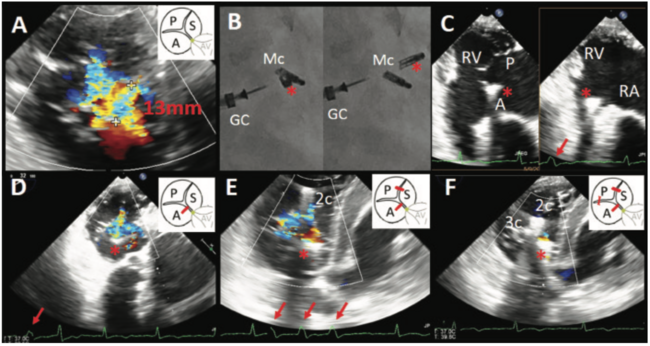

(A) Baseline TEE at transgastric short-axis view showing the widest regurgitant orifice of TR is between the anterior and septal leaflets (A = anterior; S = septal;

P = posterior leaflet; AV = aortic valve). (B) Fluoroscopy showing the flailing SLDA (* = SLDA clip; GC = guiding catheter; Mc = MitraClip placed at mitral valve).

(C) TEE showing the flailing SLDA clip everted into the right atrium where it “hit” the right ventricle, triggering premature ventricular complex (RA = right atrium; RV = right ventricle; * = SLDA clip; PVC, red arrow = premature ventricular complex). (D) TEE showing significant tricuspid regurgitation after SLDA clip deployment and the presence of PVC (red arrow). (E) TEE after second clip placed at posteroseptal commissure, showing partial stabilization of the SLDA clip and reduction of tricuspid regurgitation, but PVC persisted (red arrow = PVC; 2c = second clip). (F) Final TEE after third clip was placed at the anteroseptal commissure, which stabilized the SLDA clip and resulted in further reduction of tricuspid regurgitation and cessation of ventricular arrhythmia (3c = third clip).

A single MitraClip was deployed at the A2-P2 segments of the mitral valve, resulting in significant reduction of mitral regurgitation. Transesophageal echocardiogram revealed the widest regurgitant orifice of TR between the anterior and septal leaflets (Figure 1A, Video 1 [videos at invasivecardiology.com/multimedia]), and the first clip for TR was implanted in the anteroseptal commissure (Video 2). Despite initial successful leaflet grasping, the clip was detached from the septal leaflet after release, resulting in single leaflet device attachment (SLDA). The detached clip repeatedly “hit” the right ventricular anterior wall, triggering multiple premature ventricular complexes (PVCs) (Figures 1B-1D, Videos 3 and 4). A second clip was deployed in the posteroseptal commissure and achieved partial stabilization of the first clip, but PVC persisted (Figure 1E, Videos 5 and 6). A third clip was deployed in the anteroposterior commissure and finally stabilized the detached clip (Figure 1F, Videos 7 and 8), resulting in reduction of TR and cessation of the ventricular arrhythmias without tricuspid stenosis (mean gradient, 2 mm Hg).